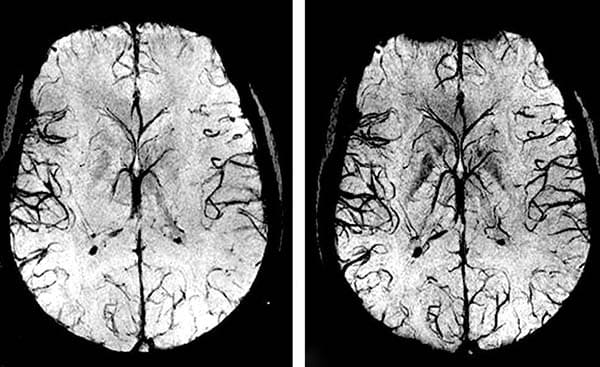

- Malattie cerebrovascolari. Sono caratterizzate da un'alterazione della vascolarizzazione cerebrale, che porta a una mancanza di nutrimento delle cellule cerebrali e al conseguente danneggiamento della materia cerebrale. Spesso queste malattie diventano causa di ictus con conseguente morte o disabilità.

Se i vasi sanguigni del cuore (arterie coronarie) sono ostruiti da depositi di colesterolo, ciò provoca inizialmente un'angina, ma in seguito può portare a un infarto del miocardio. I vasi sanguigni che non svolgono bene la propria funzione e non forniscono la giusta quantità di sangue al cervello sono una via sicura per l'ictus.